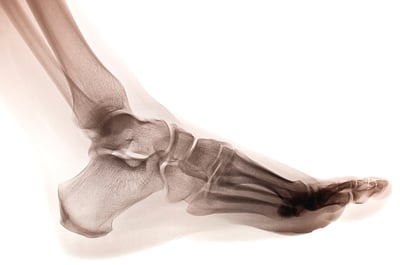

Quando se trata de treinamento atlético, os treinadores de força e condicionamento físico muitas vezes negligenciam o complexo pé-tornozelo — quando analisado adequadamente, ele fornece informações essenciais que podem ser usadas para melhorar o desempenho esportivo.

O pé em si pode ser considerado como a interface entre um atleta e o solo, ou qualquer superfície sobre a qual uma habilidade atlética é executada.

Na verdade, não é apenas a força total dessa interação que é importante, mas também como essa força é distribuída pela sola do pé, bem como o tempo e a duração do rolamento do pé. Com os avanços na tecnologia de mapeamento de pressão, é possível dividir e avaliar o pé em segmentos — retropé, mediopé e antepé, e medial e lateral — e avaliar as curvas de força-tempo e pressão-tempo para cada zona isolada.